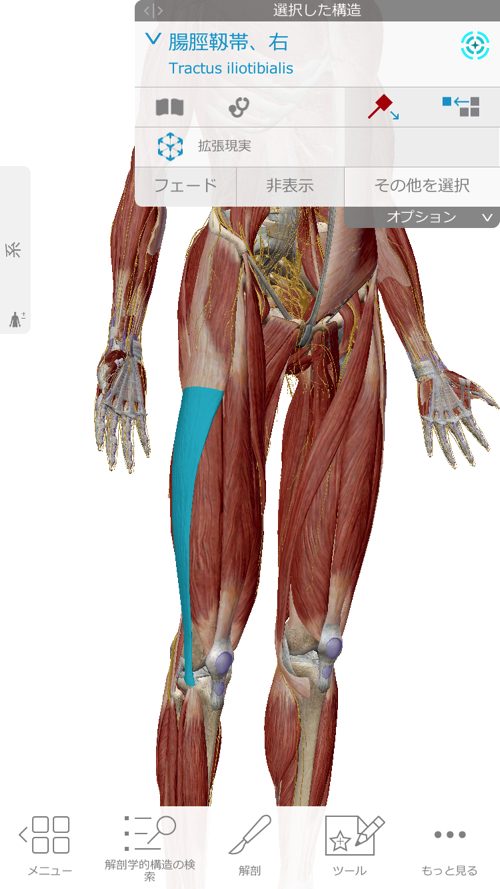

余裕が少しできたらここの靭帯を緩め

さらに膝に出来た余裕を利用してこの長腓骨筋を緩めて調整します。

今回、特にしっかりと調整したのはこの長腓骨筋です。